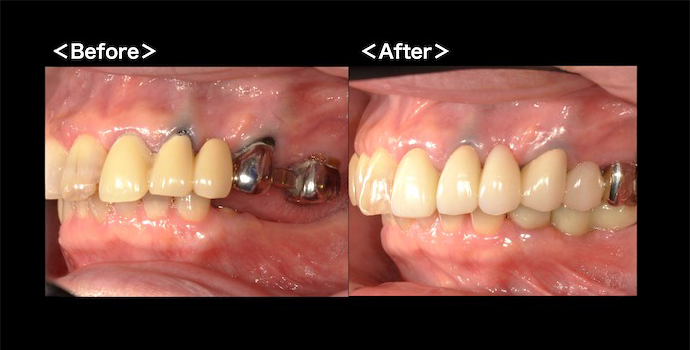

【症例】①保険診療で、できる限り白いブリッジに

患者様は左上に装着していたブリッジが虫歯になったため、新しく作り直しを希望して当クリニックを受診されました。左上1〜6番目がつながった保険診療によるブリッジで、3番目と5番目の歯が欠損していました。患者様との相談により、保険適用の硬質レジン前装冠ブリッジでの治療を選択しました。口腔内クリーニングと土台の形成後、精密な型取りを行い硬質レジン前装冠ブリッジを装着しました。保険診療の範囲内で可能な限り審美性を追求し、患者様にご満足いただける結果となった症例です。

こちらの症例の詳しい情報は下記をご参照ください。→ 【症例】保険診療で、できる限り白いブリッジに